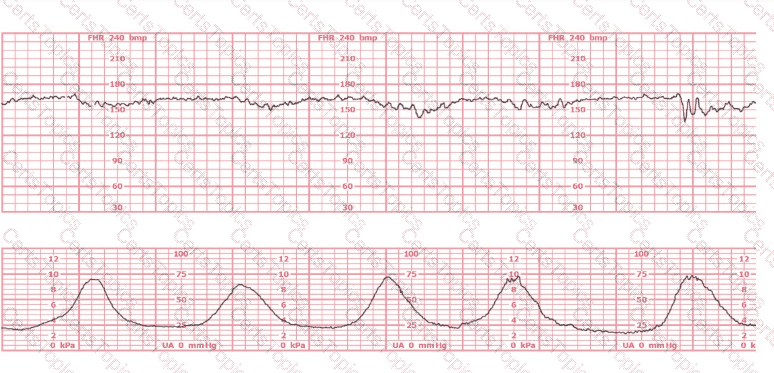

The decelerations seen in the fetal monitoring tracing shown are best described as:

A woman is admitted to labor and delivery with vaginal bleeding. This tracing is obtained. This is most consistent with:

The fetal heart rate tracing shown is obtained upon the woman's admission to labor and delivery. This tracing is most consistent with what maternal condition?

A woman at 38-weeks gestation is admitted to labor and delivery following a fall down the stairs three hours ago. She started feeling contractions in the ambulance. The fetal heart rate tracing shown is on initial evaluation and represents 25 minutes. This tracing is most consistent with a

A woman is admitted at 41-weeks gestation for fetal evaluation following a motor vehicle accident. She reports that she hit her abdomen on the steering wheel. The underlying physiology of the tracing is most likely: